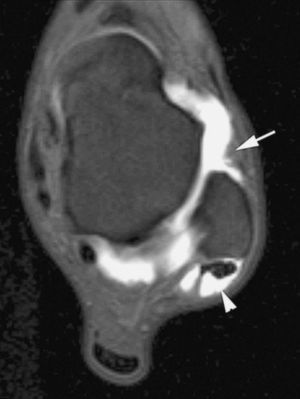

El síndrome de choque fémoro-acetabular está causado por el impacto repetido del cuello femoral sobre el borde del acetábulo debido a una alteración anatómica de la región proximal del fémur --disminución de la anteversión femoral y alteración de la relación normal entre los diámetros de la cabeza y el cuello femoral--. El tratamiento precoz de estas anomalías previene el desarrollo de coxartrosis. La RMA permite visualizar las alteraciones anatómicas del desarrollo, el estado del labrum acetabular, cartílago y cápsula articular (fig. 4)7-9.

Fig. 4.--Síndrome de choque fémoro-acetabular. Corte axial oblicuo de RMA potenciado en T1 con técnica de supresión grasa que muestra una deformidad en la transición cabeza-cuello femoral con edema focal (cabeza de flecha), formación de pequeño quiste sinovial (herniation pit), rotura del labrum antero-superior (flecha) y engrosamiento del ligamento ilio-femoral (asterisco).